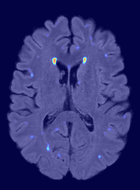

We observed that memberships predicted with an FC layer result in more false positives compared to a fully convolutional network. An example is shown in Fig. 2, where lesion memberships are generated from MPRAGE and FLAIR using the proposed model of convolutional pathways and a comparable model where the last convolutional pathway after concatenation (see Fig. 1) is replaced with a FC layer predicting voxel-wise memberships. The membership image generated with an FC layer, although being close to inside the lesions, has high values () in the left and right frontal cortex where the FLAIR image shows some artifacts. However, the membership obtained with the proposed method shows relatively low values near the frontal cortex.

With FC layer, voxel-wise predictions are performed for each voxel on a new image. Therefore the prediction time for the whole image comprising millions of voxels can take some time even on a GPU, as mentioned in Wachinger et al. (2017). In contrast, with fully convolutional prediction, lesion membership estimation of a mm3 MR volume of size takes only a couple of seconds. Note that although patches are used for training, the final trained model contains only convolution filters and does not depend in any way on the input patch size. Therefore during testing, the lesion membership of a whole 2D slice, irrespective of the slice size, is predicted at a time by applying convolutions on the whole slice. Without an FC layer, the images need not be decomposed into sub-regions, e.g., Kamnitsas et al. (2017). Consequently, there is no need to employ membership smoothing between sub-regions. In addition, since the training memberships, generated by Gaussian blurring of hard segmentations, are smooth, the resultant predicted memberships are also smooth (Fig. 2 last column).